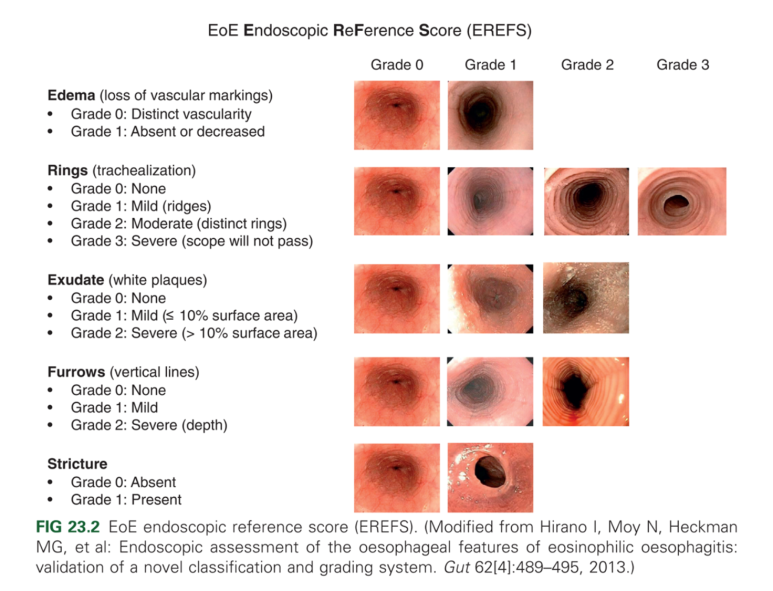

주의할 점은 내시경 소견으로 호산구 식도염을 진단해서는 안 된다는 것입니다. 예를 들면, EREFS 시스템이라는 것이 있습니다. 이 점수체계는 호산구 식도염 내시경 소견의 중증도를 점수화하여 기술하는 기준입니다. 중요한 것은 이 점수가 높다고 해서 호산구 식도염의 disease activity가 높다고 이야기하거나 관해됐다는 것을 말할 수 없다는 것입니다.